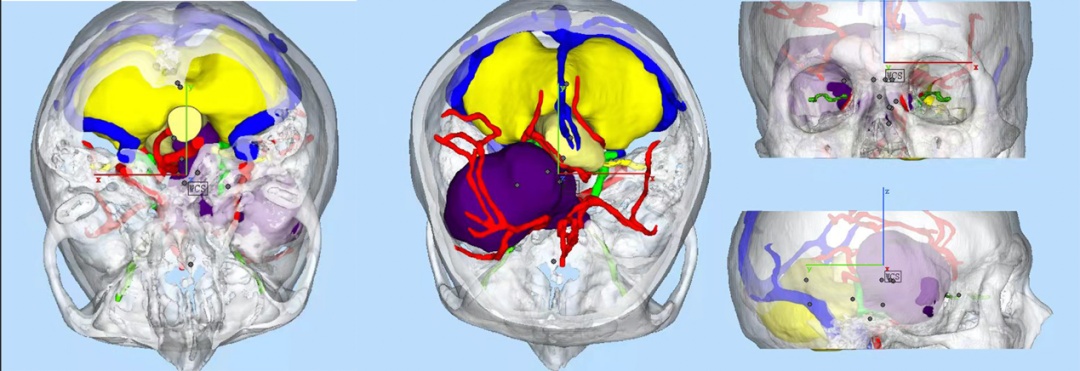

受岩骨嵴的阻挡,一期手术无法同时拆除两处“炸弹”,最终,神经外科团队医生反复推敲研判,决定分两期切除肿瘤,最大限度地降低手术风险。为此,卫永旭医生决定把通过3D建模并打印出来,这样可以看到一个很直观的病灶模型,便于术前规划。

很快,卫医生就拿到了1:1的3D打印实物,肿瘤、神经、血管错综复杂的关系清晰可见。3D打印模型,给我们在手术设计上提供了更直观的参考,对肿瘤的形态和周围结构的关系一目了然。对手术入路、切除范围、可能的风险有一个更精准的研判。